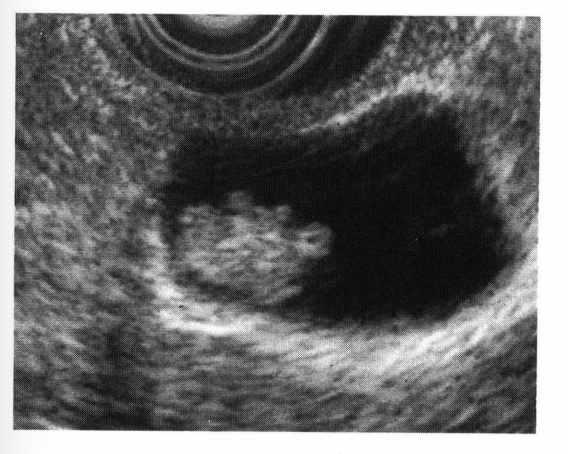

医師が胆嚢ポリープを心配している場合は、ポリープとそのサイズを診断するための検査を行うことがあります。考えられるテストは次のとおりです。

直径が 1/2 インチ未満のポリープの場合、医師は定期的な超音波検査をスケジュールして、癌を示す可能性のある変化がないか成長を監視する場合があります。医師は腹部超音波検査または内視鏡超音波検査を推奨する場合があります。

胆嚢ポリープと診断された場合、医師は超音波検査でポリープを観察することを推奨する場合があります。がんの可能性が高い場合、または胆石を患っている場合、医師は胆嚢を外科的に切除することを勧める場合があります。